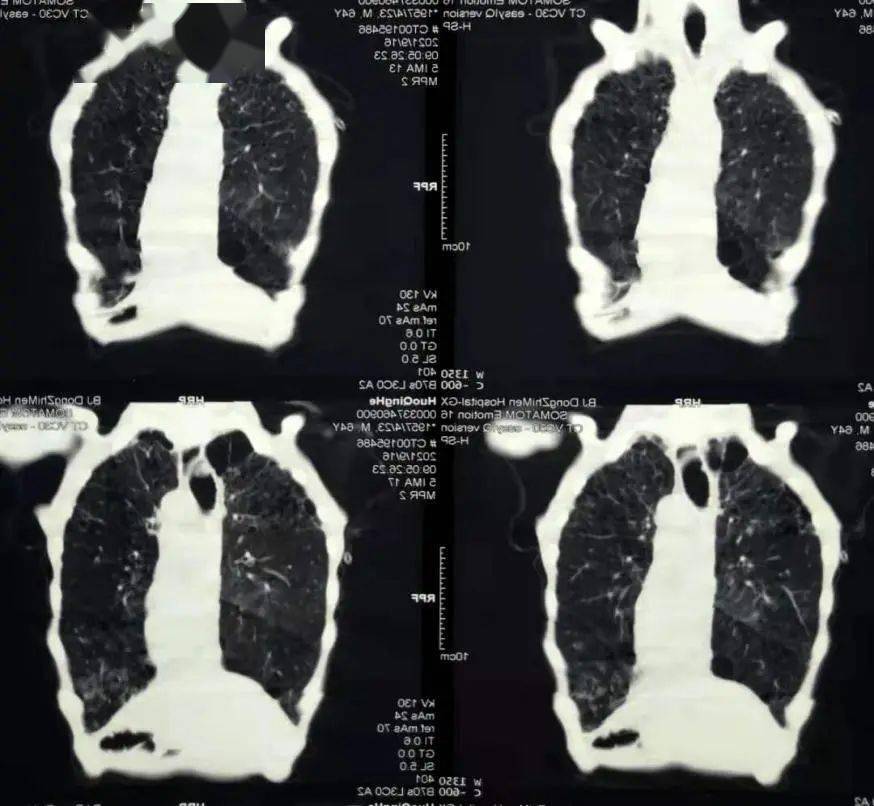

在急诊科完善了相关检查 , 上级医师刘宇此时查看了这位新来的患者 , 结合患者近期外院复查的影像发现患者下咽后壁及右侧不规则肿物 , 边界不清 , 上可达舌根部、口咽右侧壁 , 向下也已经累及会厌、右侧梨状窝、声带、室带、甲状软骨 (见红色箭头) 。 患者当前精神萎靡 , 床上稍活动后即气喘明显 , 入院查NT-proBNP水平明显升高 , 双肺CT可见肺纹理稀疏 , 多发肺大泡、小叶气肿 , 弥漫性磨玻璃小结节 , 散在斑片影 , 但是并未提示存在肺动脉高压、肺不张、气胸、大量的心包、胸腔积液等情况 。 刘宇分析病情:真假球麻痹、肺食管上纵隔肿瘤压迫喉返神经均可引发吞咽困难、声音嘶哑及饮水呛咳等症状 , 但该患者首先考虑下咽癌直接侵犯所致;中医症见神疲乏力、动则气喘、肌肤甲错 , 舌淡 , 脉沉细涩 , 属痰瘀互阻、肺肾气虚 。